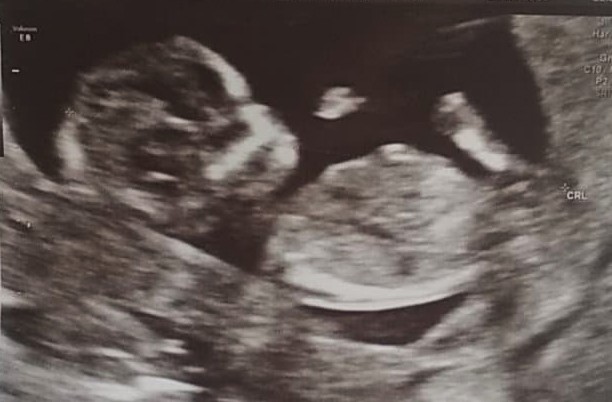

Hej dziewczyny 🙂, chciałam się przywitać i dołączyć do grupy kwietniowych mam :D 🖐. To moja pierwsza ciąża. Termin mam wyznaczony na 03.04.2021 r. (aktualnie 13+2). W tym tygodniu miałam USG prenatalne - jak na razie wszystko w porządku 🙂.

• usg.jpg

usg.jpg

44,5 KB · Wyświetleń: 83